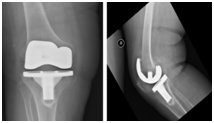

A provisional diagnosis was made for prosthetic joint infection (PJI) of the right knee and she was admitted for two-stage total knee replacement revision surgery. Her routine laboratory investigations were normal except for the erythrocyte sedimentation rate (112mm) and C-reactive protein level (44.3mg/L), which were both elevated. An analysis of knee synovial fluid aspirate indicated a normal white cell count and was negative for organisms after staining. Plain radiological investigations of the right knee showed signs of component loosening (Figure 1).

Radiographic studies, such X-rays and technetium or gadolinium bone scans, can be used in detecting prosthetic loosening, infection, or both.2,9 Weil et al.5 reported three cases of Brucella PJIs. In two of the cases, the infection developed after total knee replacement and knee radiographs revealed mild to severe bone loss and prosthetic loosening. The patient in our report had mild mechanical loosening of her knee prosthesis as shown on radiographic examination.